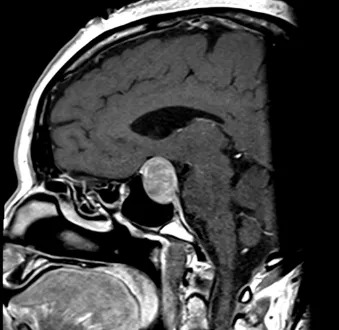

Pre- and Post-Op Pituitary Macroadenoma

Post-Op Pituitary Tumor Surgery Image 2

Post-Op Pituitary Tumor Surgery Image